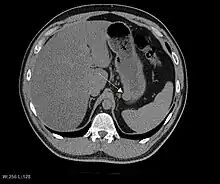

The purpose of radiologic imaging is to locate the lesion, evaluate for signs of invasion and detect metastasis. Features of GIST vary depending on tumor size and organ of origin. The diameter can range from a few millimeters to more than 30 cm. Larger tumors usually cause symptoms in contrast to those found incidentally which tend to be smaller and have better prognosis.[4][13] Large tumors tend to exhibit malignant behavior but small GISTs may also demonstrate clinically aggressive behavior.[14]

Barium fluoroscopic examinations and CT are commonly used to evaluate the patient with abdominal complaints. Barium swallow images show abnormalities in 80% of GIST cases.[14] However, some GISTs may be located entirely outside the lumen of the bowel and will not be appreciated with a barium swallow. Even in cases when the barium swallow is abnormal, an MRI or CT scan must follow since it is impossible to evaluate abdominal cavities and other abdominal organs with a barium swallow alone. In a CT scan, abnormalities may be seen in 87% of patients and it should be made with both oral and intravenous contrast.[14] Among imaging studies, MRI has the best tissue contrast, which aids in the identification of masses within the GI tract (intramural masses). Intravenous contrast material is needed to evaluate lesion vascularity.

Preferred imaging modalities in the evaluation of GISTs are CT and MRI,[16]: 20–21 and, in selected situations, endoscopic ultrasound. CT advantages include its ability to demonstrate evidence of nearby organ invasion, ascites, and metastases. The ability of an MRI to produce images in multiple planes is helpful in determining the bowel as the organ of origin (which is difficult when the tumor is very large), facilitating diagnosis.

Large GISTs

As the tumor grows it may project outside the bowel (exophytic growth) and/or inside the bowel (intraluminal growth), but they most commonly grow exophytically such that the bulk of the tumor projects into the abdominal cavity. If the tumor outstrips its blood supply, it can necrose internally, creating a central fluid-filled cavity with bleeding and cavitations that can eventually ulcerate and communicate into the lumen of the bowel. In that case, barium swallow may show an air, air-fluid levels or oral contrast media accumulation within these areas.[14][17] Mucosal ulcerations may also be present. In contrast-enhanced CT images, large GISTs appear as heterogeneous masses due to areas of living tumor cells surrounding bleeding, necrosis or cysts, which is radiographically seen as a peripheral enhancement pattern with a low attenuation center.[13] In MRI studies, the degree of necrosis and bleeding affects the signal intensity pattern. Areas of bleeding within the tumor will vary its signal intensity depending on how long ago the bleeding occurred. The solid portions of the tumor are typically low signal intensity on T1-weighted images, are high signal intensity on T2-weighted images and enhanced after administration of gadolinium. Signal-intensity voids are present if there is gas within areas of necrotic tumor.[15][18][19]

Malignancy is characterized by local invasion and metastases, usually to the liver, omentum and peritoneum. However, cases of metastases to bone, pleura, lungs and retroperitoneum have been seen. In distinction to gastric adenocarcinoma or gastric/small bowel lymphoma, malignant lymphadenopathy (swollen lymph nodes) is uncommon (<10%) and thus imaging usually shows absence of lymph node enlargement.[13] If metastases are not present, other radiologic features suggesting malignancy include: size (>5 cm), heterogeneous enhancement after contrast administration, and ulcerations.[4][13][20] Also, overtly malignant behavior (in distinction to malignant potential of lesser degree) is less commonly seen in gastric tumors, with a ratio of behaviorally benign to overtly malignant of 3-5:1.[4] Even if radiographic malignant features are present, these findings may also represent other tumors and definitive diagnosis must be made immunochemically.